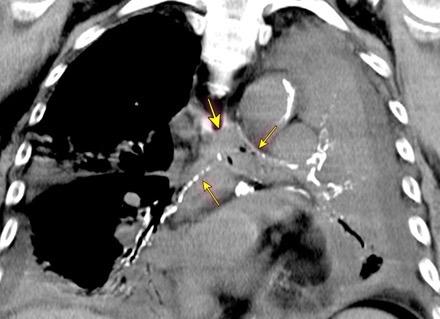

Edad: 40-50 años

3% segregan catecolaminas.

(En el área Paravertebral +/-50%.)

Intenso realce con el contraste.

32 años .Preeclampsia a los 19. Hipertensión no controlada. Masa paravertebral sólida que se realza intensamente con afectación ósea.

Yue Y t al. Asymptomatic left posterior mediastinal functional Paraganglioma. A case report. Medicine . 2019